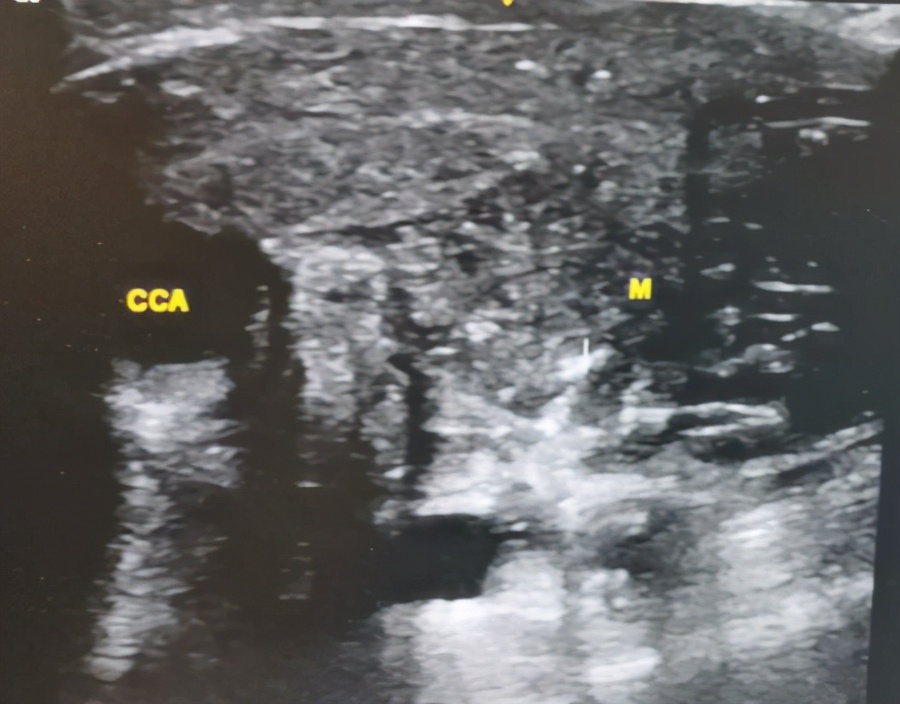

超声联合纤支镜引导下经皮气管切开

复发的肿瘤及周围组织

张波涛为主任做彩超评估

徐兰娟为病人做气管切开